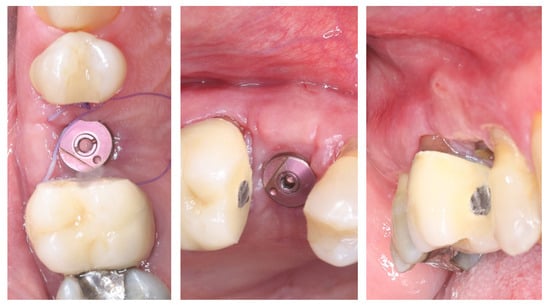

Figure 11 illustrates the peri-implant soft tissue condition 14 days after simultaneous implant placement and roll flap augmentation at suture removal. The buccal flap shows uneventful healing with adequate tissue thickness and favourable contouring around the healing abutment. The mucosal margin appears stable, with absence of dehiscence or inflammation, indicating successful integration of the rolled flap. Different views demonstrate proper adaptation of the peri-implant mucosa, confirming the effectiveness of the roll flap in enhancing buccal soft tissue thickness and achieving a harmonious gingival architecture.

Figure 11.

Clinical views before and after suture removal (14 days post-op).

Three months postoperatively, the peri-implant site demonstrates complete mucosal healing with stable, well-contoured soft tissues. The healing abutment is visible in situ (left), with healthy, keratinized mucosa surrounding the transmucosal interface. Following removal of the healing abutment (middle), the implant platform shows a mature and stable soft tissue collar without signs of inflammation, recession, or dehiscence. The X-ray control reveals stable crestal bone levels without signs of bone remodelling (right) (Figure 12). The roll flap augmentation resulted in increased buccal tissue thickness and harmonious gingival architecture, providing favourable conditions for prosthetic restoration.

Figure 12.

Mature peri-implant mucosa and stable crestal bone after roll flap augmentation (3 months post-op).